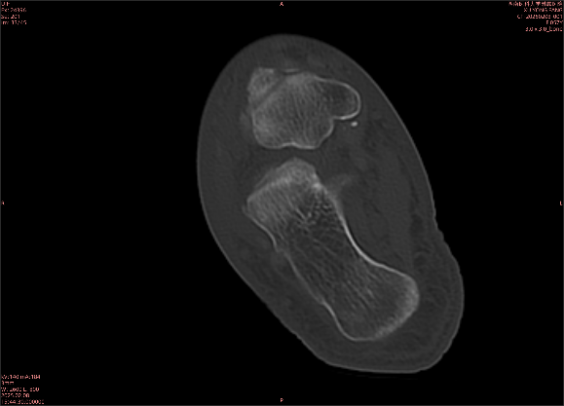

舉例圖像

圖2

專業(yè)解釋看不懂沒關(guān)系,大家看圖1和圖2就可以了,這是同一個(gè)患者跟骨的磁共振和CT圖像,圖1的紅色箭頭指示的黑線就是磁共振圖像顯示的骨折線,一目了然。而對比圖2的CT圖像上并未顯示異常。